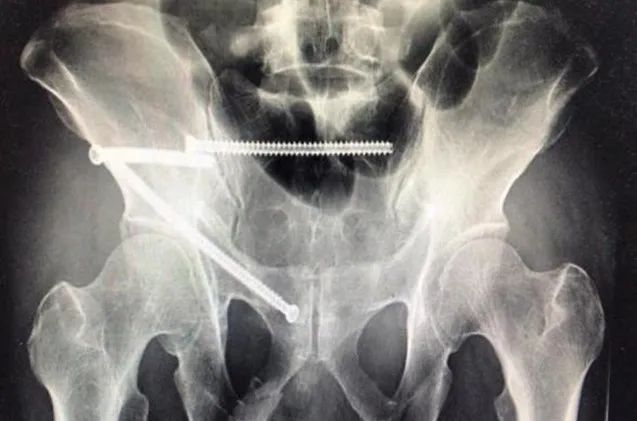

36岁的患者卢某某,在干活时被重物砸伤。经过影像检查,诊断为骨盆C型骨折,收治到骨科病区。传统手术下,需要卧床三四个月,作为家中的顶梁柱,患者内心十分焦急。科主任李志永、副主任医师陈学青仔细分析了患者的病情,经过与患者及家属多次沟通,决定为其行在多角度透视引导下微创骶髂螺钉、耻骨上支螺钉、LC-II螺钉内固定术。完善术前各项术前准备后,患者被推进手术室。手术只需要在臀部打开一个1厘米的小口,在透视下用螺钉将骶骨和髂骨连接固定。手术过程中,螺钉从髂骨出发,避开错综复杂的静脉和动脉血管、骶管中的马尾神经、骶孔中的神经等。每走一小步,都需要进行多角度的透视,以避免损伤血管和神经。就这样,螺钉小心翼翼到达骶骨,完成固定。这个过程对术者的技术是极大的挑战。随后,患者又完成了耻骨上支螺钉、LC-II螺钉内固定术,这台三合一的手术历时了2个小时顺利完成,整个手术过程出血约50毫升。

多角度透视引导下微创骶髂螺钉、耻骨上支螺钉、LC-II螺钉内固定手术固定相比较其他固定方式更加牢靠,创伤小、出血少、恢复快,克服了切开复位钢板内固定或腰骶钉棒固定引发的诸多并发症。尤其对老年骨盆骨折的患者,具有更大优势。未来此项微创固定技术手术时间和精准度会更加提高。